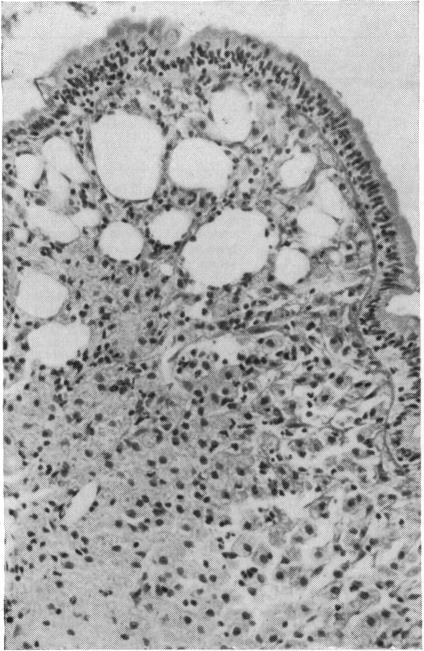

Two cases of Whipple's disease are reported in which a parallel course is confirmed between the clinical and ultrastructural findings. This is not so with light microscopy since it takes much longer for these findings to return to normal. In case 1, the presence of bacilli circulating freely in the sinusoid of a lymph node is described. Case 2 demonstrates the existence of special granulomata formed by atypical macrophage histiocytes which appear in coagulative necrosis together with a closely adherent crown of lymphocytes. Furthermore, these histiocytes have moved towards the deepest part of the lamina propria, and have become dissociated from the muscularis mucosae causing a diverticulosis of the small intestine.

报告了两例惠普尔病,其临床和超微结构检查结果呈现平行关系。而光学显微镜检查则不然,因为这些结果恢复正常所需时间长得多。病例1描述了杆菌在淋巴结窦中自由循环的情况。病例2显示了由非典型巨噬细胞组织细胞形成的特殊肉芽肿的存在,这些细胞与紧密附着的淋巴细胞冠一起出现在凝固性坏死中。此外,这些组织细胞已向固有层最深部移动,并与黏膜肌层分离,导致小肠憩室形成。